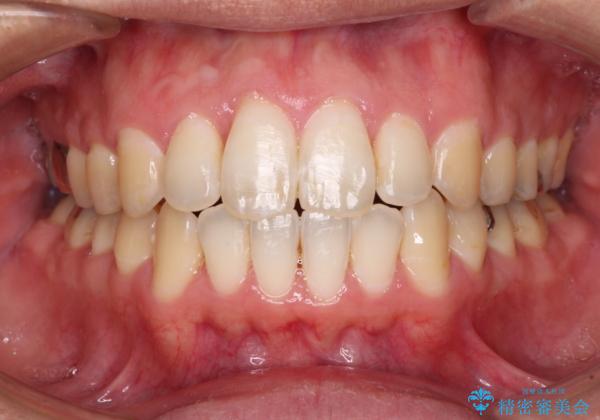

上顎奥歯付近にアンカースクリューを用い、上顎歯列全体の後方移動と、大臼歯圧下を促し、前歯の上下関係を改善することとしました。

奥歯には目立つ銀歯が多くあるので、矯正治療後には下顎の銀歯をセラミッククラウンやセラミックインレーにより、補綴・修復治療することとしました。

上顎歯列全体を後方に移動させたため、口元の突出感も改善され、装置を外してからは口が閉じやすくなりました。

また、上下犬歯が接触するようになったため、奥歯にストレスのかからない歯ぎしりができるようになり、顎の疲れも改善されました。